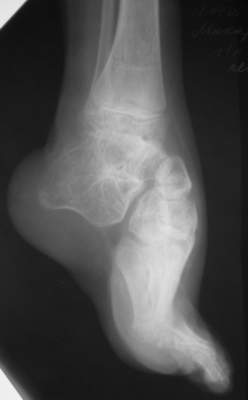

Уважаемые коллеги,Ребенок, мальчик, 11 лет...Врожденная косолапость,до 4 лет лечился консервативно, в 4 года оперирован у нас - операция по типу Зацепина, далее аппаратИлизарова...Предоперционная картина - как на рис "case 1 a" (фото другогобольного)...При операции использовался аппарат с "моноблоком" стопы -см. "case 1 b" (фото другого больного) -в связи с чем интраоперационно провели достаточно выраженную одномоментнуюкоррекциюпосле чего возник некроз в областиоперационных ран в результате чего "вывалился" "кусок" по внутреннейповерхностих...аппарат сняли... больного перевели в отделениемикрохирургии... с другой голени делали пересадку... прижилось...больного выписали...все это было 7 лет назад...3 года назад больной лечился в Астрахани...Никаких выписок нет (не видел...)(хэллоу, астраханцы!!! если есть - отзовитесь...),но со слов мальчика и его матери ему делали удлинение на уровневерхней трети голени плюс исправляли стопу... опять-таки со слов -сразу же после коррекции стопу загипсовали на 6 нед, после чегопрописали ночные тутора плюс ортообувь... т.е. после коррекции стопу ваппарате не выдерживали и гипсовали всего 1,5 мес.... через 6 месстопа "ушла" в исходное положение...с которой он пришел к нам сейчас... (case 2-9)В настоящее время у мальчика эквино (!!!)-варус... в подтаранномсуставе полный анкилоз... (см. Ro)Были предложения исправить деформацию аппаратно с остеотомией черезладью...Передумали:-)...Лично у меня возникают также вопросы на счет плюсне-клиновидныхсусутавов... и так я их Ro-фировал, и эдак (снимки не представлены), авсе равно не могу избавиться от впечталения, что и в них имеется некоефиброзно-костное анкилозирование...А на КТ у больных денег нету...Короче...Наложили аппарат...Попытаемся растянуть стопу + "подкоррегировать" варус иубрать эквинус...А после этого определиться с уровнем остеотомии (это официальноемнение...)Я же хочу сделать все тоже, за исключением остеотомии (при условии чтонет того самого анкилозирования на уровне плюсне-клиновидныхсусутавов...)Убрать варус и эквинус на фоне удлинения...коррекция с гипер-...плюс подержать в этом положении 1-1,5 мес...Но не лежит рука к остеотомии...Единственное, после коррекции есть желание "отсепарировать" подошвенные связки с костной "основой" от пяточной кости и загипсовать в таком положении во избежание возможного рецидива...А там посмотрим...мнения ???

Слушал сообщение на ЭФОРТе в 2001 году, по упомянутой теме из продемонстрированные результаты постепенной коррекции регидных деформаций прозвучали очень оптимистично, демонтсрация картинок прооопрерованных детей 9-13 лет - варус и эквинус откоррегирован. после снятия аппарата практиковались сменные этапные гипсовые повязки до года.

Как вариант при запущенных ригидных деформациях применялась Эванс остеотомия пяточно-кубовидного сустава с фиксацией скобкой в сочетании с задне-медиальным релизом и гипсовой иммобилизацией 4 недели. У одного ребенка с артрогрипозом (аналогичная деформация представленная на

первой фотографии) была произведена первичная талэктомия с восстановлением подошвенной установки стопы.